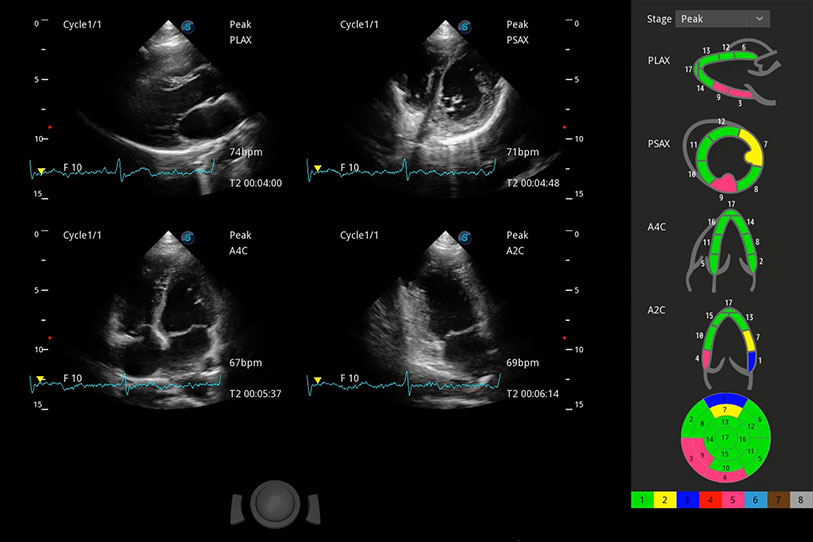

能夠基于左心室壁追蹤和辛普森法,自動計(jì)算射血分?jǐn)?shù),支持多個可移動點(diǎn)描跡,與手動測量相比,極大節(jié)省了動物醫(yī)生的時(shí)間和精力。

具備多種協(xié)議可選,同時(shí)支持17階段劃分法和專業(yè)的SE報(bào)告。